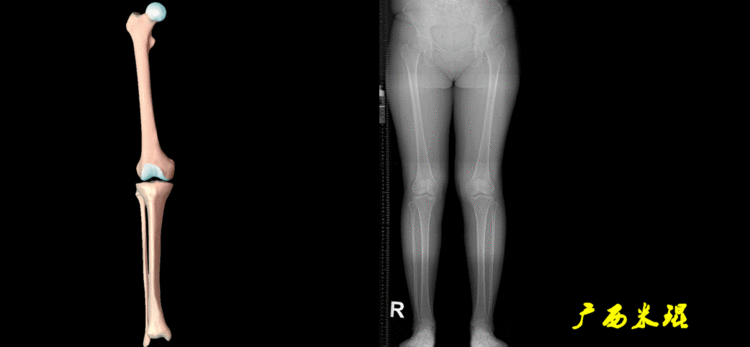

无论如何,拍摄出来的下肢全长片必须包含髋关节中心、膝关节中心及踝关节中心,否则对临床是无用的。有了一张下肢的全长照片,我们需要确定下肢关节的中心点,通过中心点画出下肢的各种轴线,然后利用轴线与关节线的相交得出各种所需要的角度。

1、确定下肢关节的中心点(1)髋关节中心髋关节中心点由股骨头来确定,由于股骨头是相对比较规则的圆形,使用Mose圈或圆规就能确定股骨头中心也就是髋关节中心。

(2)膝关节中心膝关节中心点常用的有5个不同的定位方法,分别是股骨髁中点、股骨髁间窝顶点、膝关节间隙水平软组织中点、胫骨髁间嵴中点和胫骨平台中点,我们可以根据具体情况来选用。

(3)踝关节中心踝关节中心点常用的也有3个,分别是骨骼(内、外踝表面间距)中点、踝关节间隙水平软组织中点和距骨宽度中点。

2、画出下肢的轴线确定髋关节、膝关节、踝关节的中心点后,我们才能了解下肢的几个轴线。(1)解剖轴股骨和胫骨的骨干中线为解剖轴,股骨解剖轴和胫骨解剖轴的夹角正常值为174°±1°。

(2)机械轴机械轴是连接近端和远端关节中心点的直线。

机械轴要分前后位及侧位,站立前后位(也就是冠状面)股骨头中心与踝关节中心的连线通过膝关节中心,这是下肢的机械轴线,也就是下肢力线,常说Mikulicz线。冠状面的力线评估在临床工作中最常用、最基础、最重要。